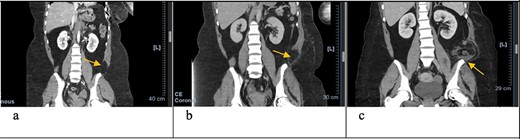

Axial CT scan with arrows pointing to internal and external oblique defects in June (a), August (b) and September (c); panel (a) shows rupture between internal and external oblique muscles at the attachment point of the quadratus lumborum; panel (b) shows fat stranding, suggesting inflammation of the epiploic appendage, and may be an early sign of delayed traumatic wall hernia; panel (c) shows herniation through the muscular defect.

In June, the patient’s CT imaging demonstrated a left posterolateral muscular defect of the fascia and external and internal obliques (Figs 1a and2a). Follow-up CT in August showed an increase in size with noticeable atrophy of the muscles with fat stranding (Figs 1b and2b). The atrophy may be due to the month-long period where she was immobile in the SICU. Muscle atrophy combined with the inciting event could be indicators for delayed TAWH, especially for those with prolonged hospital stays [3, 10]. When the hernia presented, CT imaging showed the appearance of fat and descending bowel (Figs 1c and 2c). We theorize that our patient’s MVC resulted in an initial defect or tear in the fascia, internal and external obliques. Her prolonged stay compounded the problem through muscle atrophy and peritoneal stretching. These factors, coupled with the activities of daily life, lead to the delayed presentation of traumatic lumbar hernia. Although lumbar hernias may rarely cause SBO, they may be indirectly linked.